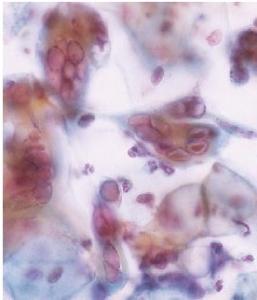

Les chercheurs d'Helsinki ont cherché à identifier les facteurs cellulaires impliqués dans la réactivation du virus KSHV à l'aide de technologies de microscopie avancées et de manipulation génétique. Leurs travaux montrent qu'une grande variété de composés chimiques conduisent à l'activation d'un ensemble de protéines (p53 et p21clip) dites capteurs de stress cellulaire et dont la fonction est de protéger la cellule du stress en ralentissant la prolifération cellulaire. Ce processus semble créer un environnement qui favorise la réactivation du génome viral ce qui conduire à d'énormes dégâts de l'ADN cellulaire et stopper le cycle de division dans un état connu comme « G2 ». Et, dans cet état, les ressources cellulaires sont concentrées dans l'assemblage de milliers de nouveaux virions…Les chercheurs montrent que la suppression par manipulation génétique des fameuses protéines capteurs de stress cellulaire restaure la division cellulaire dans les cellules et réduit l'expression du gène viral, ce qui suggère que la réplication de KSHVdépend de l'inhibition de la division cellulaire.